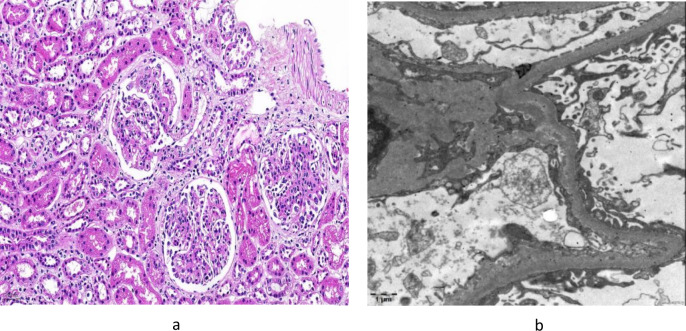

IgA vasculitis (IgAV) is the most prevalent form of vasculitis in children. While most cases of IgAV present with mild clinical symptoms and generally have a favorable prognosis, some children with IgAV nephritis may experience persistent heavy proteinuria, which is at risk of progressing to end-stage renal disease. Despite the administration of various immunosuppressive agents, treatment outcomes for these children are often suboptimal. We report the case of an 8-year-and-four-month-old girl who initially presented with rashes on both lower limbs for a duration of four days and abdominal pain persisting for two days. Renal biopsy subsequently confirmed a diagnosis of IgAV nephritis, specifically type IIIb. Despite undergoing treatment with methylprednisolone sodium succinate, cyclophosphamide, mycophenolate mofetil, leflunomide, rituximab, dapagliflozin, and other medications for over two years, her urinary protein levels remained at least 1000 mg/24 h. One month after initiating treatment with telitacicept, the patient's urinary protein levels decreased, and two months later, they became negative. Notably, even after discontinuing immunosuppressants and glucocorticoids, the girl achieved sustained clinical remission. This case serves as a valuable clinical reference for the use of telitacicept in the treatment of refractory IgAV nephritis.